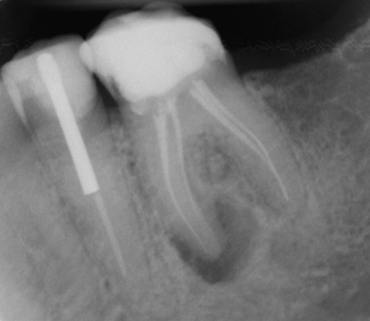

1.Prima Visita e Diagnosi

Il primo passo è una diagnosi accurata, anche con l’aiuto di una radiografia specifica, che ci permette di visualizzare le radici del dente e confermare la necessità del trattamento endodontico.